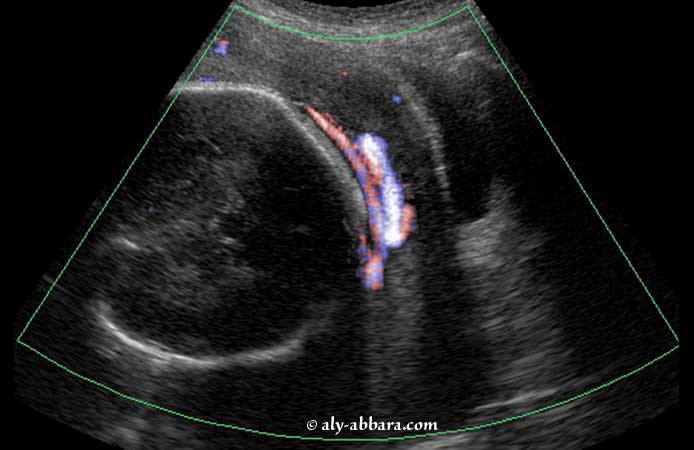

Vasa prævia (vaisseaux prævia)

• Images échographiques à 31,5 SA mettant en évidence de multiples vaisseaux prævia associés à un placenta bas inséré postérieur de type I, avec un cotylédon aberrant antéro-latéral gauche. L'échographie fut réalisée à ce terme de grossesse dans le cadre d'une nouvelle exploration étiologique de métrorragies de très faible importance et de très courte durée (de quelques heures), ayant eu lieu une semaine auparavant, sans modifications cervicales ni anomalies du rythme cardiaque fœtal.

• A 38 SA, le placenta, échographiquement n'est plus bas inséré, mais le diagnostic de vasa prævia fut toujours d'actualité, donc une césarienne programmée fut réalisée à ce terme ; l'examen macroscopique des annexes fœtales confirme le diagnostic échographique en mettant en évidence l'insertion marginale du cordon (en raquette), avec un réseau vasculaire composé d'artères et de veines reliant le cotylédon aberrant au cordon ; l'extraction chirurgicale fœtale aboutit obligatoirement à l'ouverture de la poche des eaux avec la rupture de quelques-uns des ces vaisseaux prævia.

• Le nouveau était en parfaite santé sans anémie ; son extraction par césarienne permit d'éviter l'hémorragie de Benckiser qui pouvait lui être fatale.